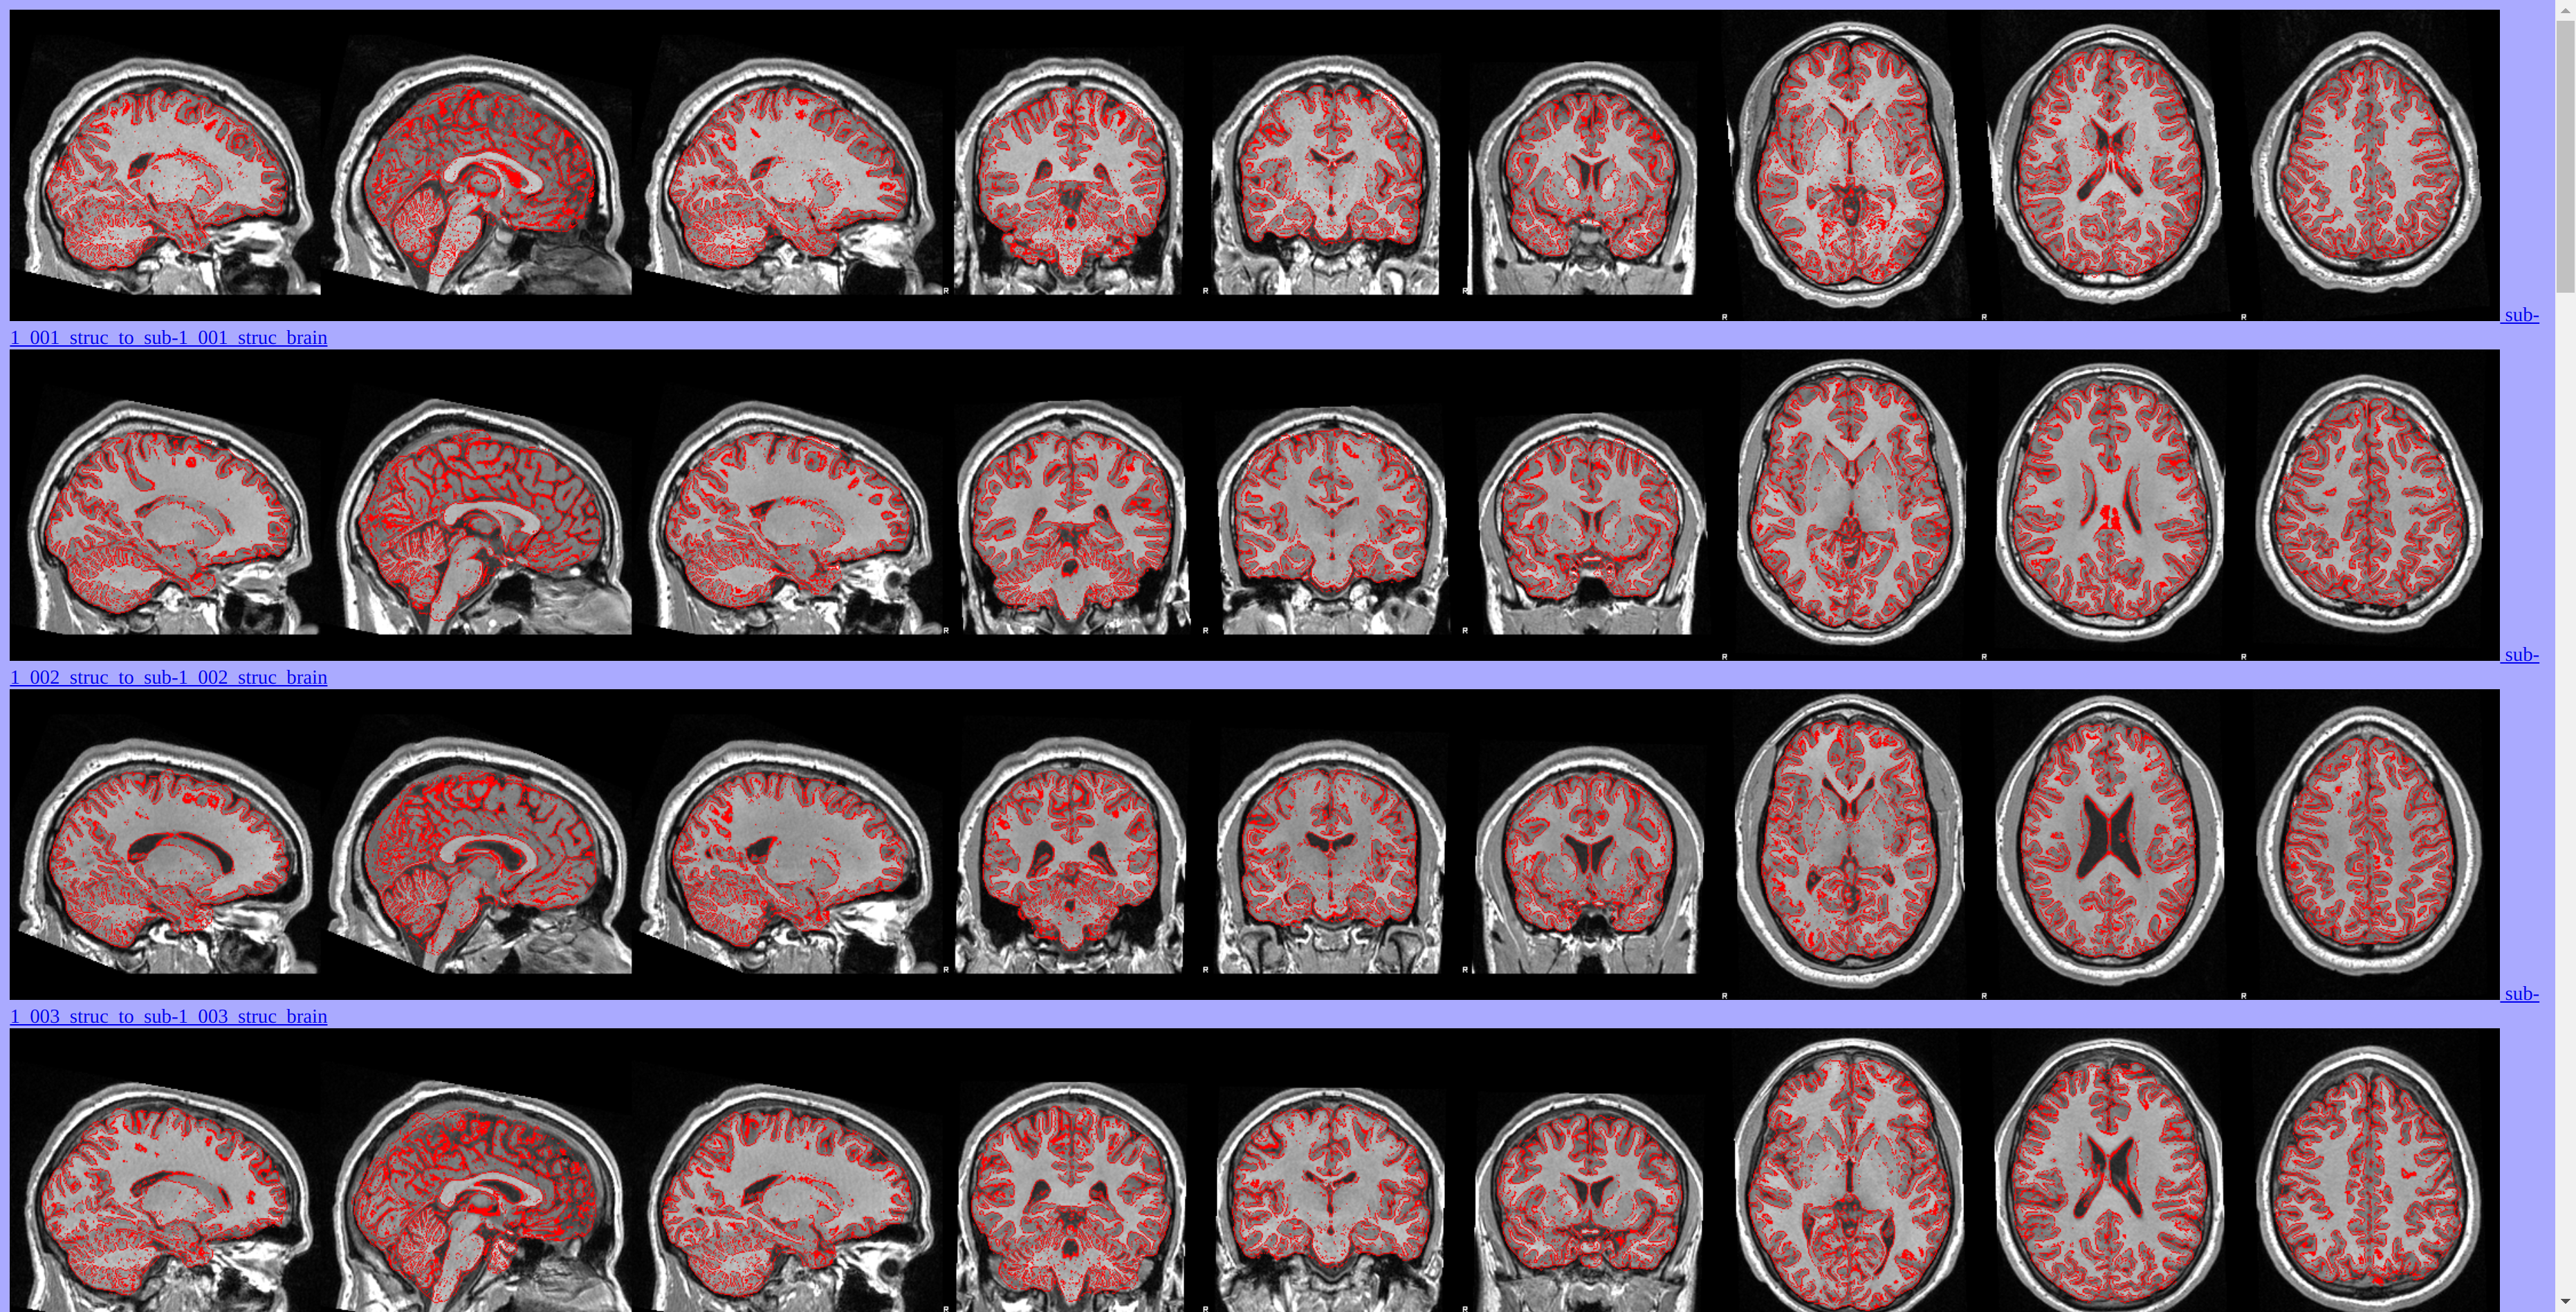

MRI data have been preprocessed using FSL tools.

Voxel-Based Morphometry (VBM) Analysis

Grey matter volume differences between athletes and non-athletes have been investigated using FSLVBM [FMRIB’s Software Library - Voxel-Based Morphometry]